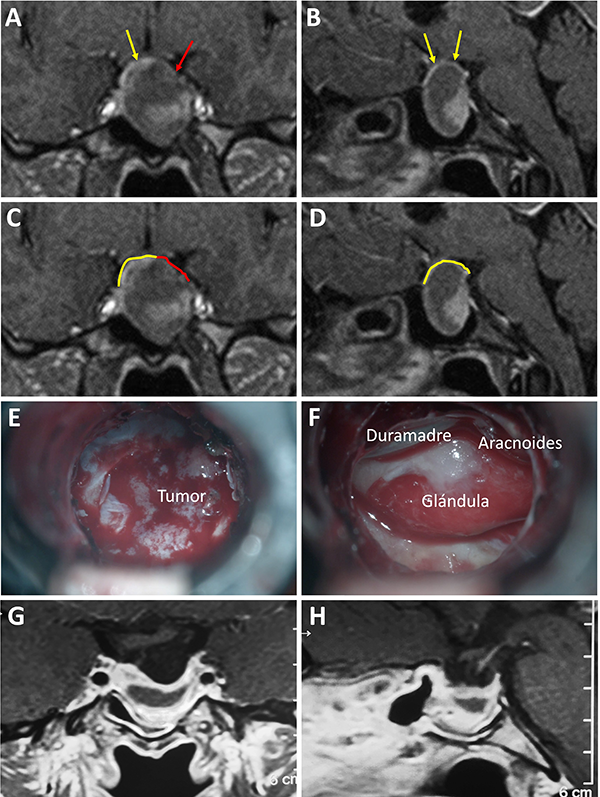

Una clasificación clásica de los adenomas es según su tamaño. Se los clasifica en microadenoma <10 mm (fig. 2), macroadenoma >10 mm (fig. 3), y adenoma gigante > 30 mm (fig. 4). Esta clasificación es importante ya que los índices de remisión están ligados al tamaño del adenoma y también su recidiva.12

Figura 3: Macroadenoma. A-B: RM preoperatoria; C-D: Campo visual preoperatorio; E-F: RM postoperatoria; G-H: Campo visual postoperatorio.

El techo de la fosa pituitaria está constituido en condiciones normales por un máximo de 2 estructuras: duramadre (diafragma selar) y aracnoides.65,66 En condiciones patológicas, cuando existe un adenoma hipofisario, éste empuja hacia arriba a la glándula. De este modo, la interfase entre el tumor y el LCR se encuentra constituida por un máximo de 3 elementos: glándula, duramadre y aracnoides. Cabe destacar que la aracnoides es el único elemento constante. A los elementos que constituyen esta interfase el equipo de Tucumán los denominó “barrera selar”.11,60

Existen 3 subtipos de barrera selar según los hallazgos intraoperatorios, luego de resecar el tumor:

Un factor interesante de este novedoso concepto es que el tipo de barrera puede evidenciarse en la RM preoperatoria. De este modo, existen 3 subtipos de barrera selar según la radiología:

Los pacientes con una barrera débil tienen mayor riesgo de fístula intraoperatoria de LCR. La barrera fuerte es un factor protector de fístula de LCR.11,60

Figura 6: Barrera selar fuerte. A-B) RM preoperatoria. C-D) Hallazgos intraquirúrgicos. E-F) RM postoperatoria. Flechas amarillas: interlinea > 1mm. Tomado de Campero A, Villalonga JF, Basso A. Anatomical risk factors for intraoperative cerebrospinal fluid leaks during transsphenoidal surgery for pituitary adenomas. World Neurosurg. 2019;124:346-55.

Figura 7: Barrera selar mixta. A y C) RM preoperatoria corte coronal; B y D) RM preoperatoria corte sagital; E-F) Hallazgos intraoperatorios; G-H) RM postoperatoria. Flechas y líneas: color rojo indican barrera débil; color amarillo indican barrera fuerte. Tomado deVillalonga JF, Ries-Centeno T, Sáenz A, Solari D, Cervio A, Campero A. The mixed sellar barrier: a new subtype of this novel concept. World Neurosurg. 2019;132:5-13.

Figura 8: Barrera selar débil. A-B) RM preoperatoria; C-D) Hallazgos intraoperatorios. E-F) RM postoperatoria. Flechas rojas: interlínea < 1mm. Tomado de Campero A, Villalonga JF, Basso A. Anatomical risk factors for intraoperative cerebrospinal fluid leaks during transsphenoidal surgery for pituitary adenomas. World Neurosurg. 2019;124:346-55.